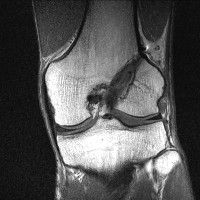

무릎 mri 간단히 봐주실 수 있으시나요 ㅠㅠ

안녕하세요 8년전 십자인대 수술하고 최근 무리한 운동에 무릎 불편감이 생겨서

mri 찍었습니다.

진단결과는 첫 찍은 병원에서 활액막염 이라는 진단을 받았습니다. 혹시 봐주실 수 있으실까요?

올라온 MRI가 단편적이라서 정확한 진단에 어려움이 있지만 십자인대에는 큰 이상이 있지는 않은것 같으며, 무릎관절내 물이 있는 것으로 보아 활액막염의 진단이 맞을 것 같습니다.

하지만 단편적인 영상이기 때문에 촬영병원에서 정확한 판독지 등을 받으시는 것이 좋겠습니다.